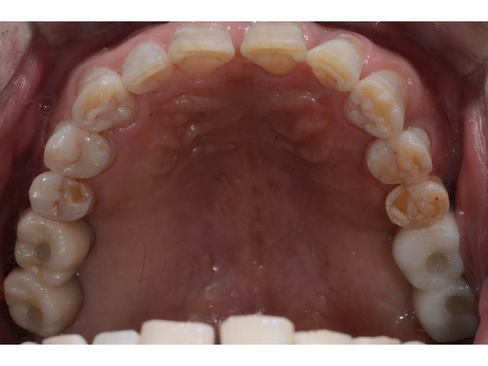

Pre-operative intraoral view